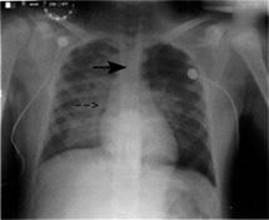

Chest x-ray (Figure 12-4):

FIGURE 12-4. Chest x-ray demonstrating diffuse bilateral pulmonary infiltrates.

Note tip of endotracheal tube (arrow) is in good position.